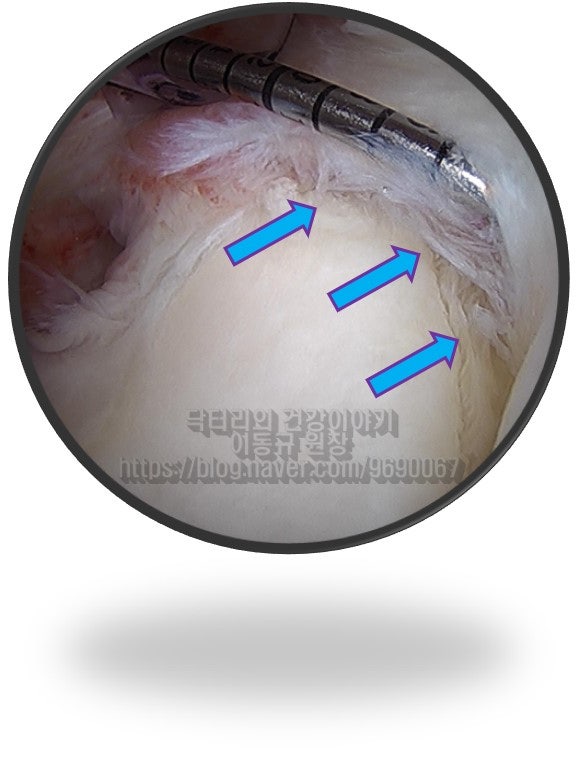

경추부 X-ray 와 MRI 도 확인했으나 특이소견은 없었습니다. 즉 이 환자분은 조금 특이한 위치에 석회가 있으면서 어깨 통증을 유발된 환자고 위치적으로 상견갑신경과 비슷한 위치에서 염증을 일으키다 보니 경추부 문제로 오진되어 치료를 제대로 받지 못했던 경우로 판단됩니다. 위치적으로 뉴핌스치료(석회분쇄흡입술)을 할 수 없는 위치이며 상부관절와순 손상에 대한 치료를 동시에 하기 위해 수술적 치료를 결정하였습니다.

환자는 수술 후 이전에 느꼈던 통증이 해소 되었다며 무척이나 만족해 하셨습니다. 아파서 좋아하던 운동도 못하고 우울증도 왔다면서 힘들어 하면서 저한테 오셨는데 이제는 재활 열심히 해서 다시 운동할 수 있다고 하니 너무너무 고마워 하셨습니다. 세상에 똑같은 병은 없습니다. 그렇기에 이야기를 잘 듣고 면밀히 검사하는 것이 중요합니다. 단순히 영상 자료만으로 환자의 병을 진단해서는 안된다고 생각합니다. 환자의 증상을 정확히 듣고 이학적 검사를 통해 증상을 확인하고 영상 자료와 같이 확인하고 판단해야 합니다.